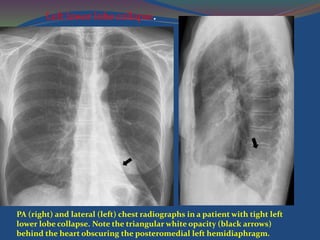

PA (right) and lateral (left) chest radiographs in a patient with tight left

lower lobe collapse. Note the triangular white opacity (black arrows)

behind the heart obscuring the posteromedial left hemidiaphragm.

Left lower lobe collapse.